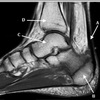

5

Perfectly

12

Q

What is letter B?

A

BICEPS TENDON (LONG HEAD)

How well did you know this?

1

Not at all

2